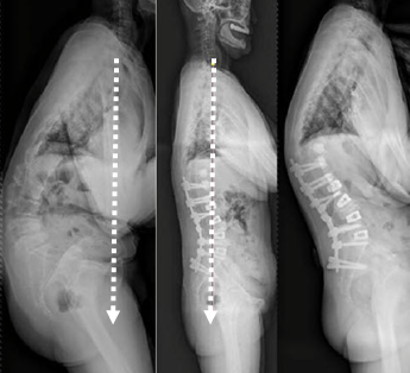

(1)长节段固定/固定到骶骨的节段固定

图5 脊柱远端融合节段越多,如包括L5-S1水平固定到骶骨或髂骨,发生交界性后凸的可能性越大

2.减少融合节段,尽量保留远端活动节段以降低近端应力

图24 左:长节段固定至髂骨;右:长节段固定